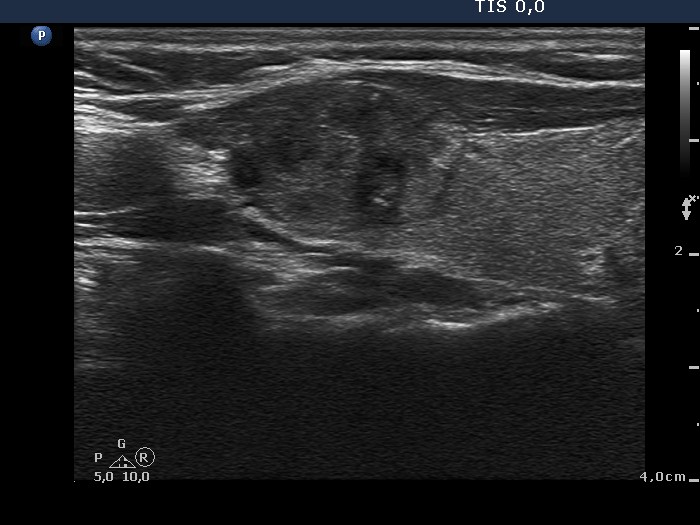

Ultrasonography: there was a moderately hypoechogenic nodule with irregular borders and combined type 2 and type 3 vascular patterns in the lateral part of the right thyroid. There were two lymph nodes above the right thyroid.